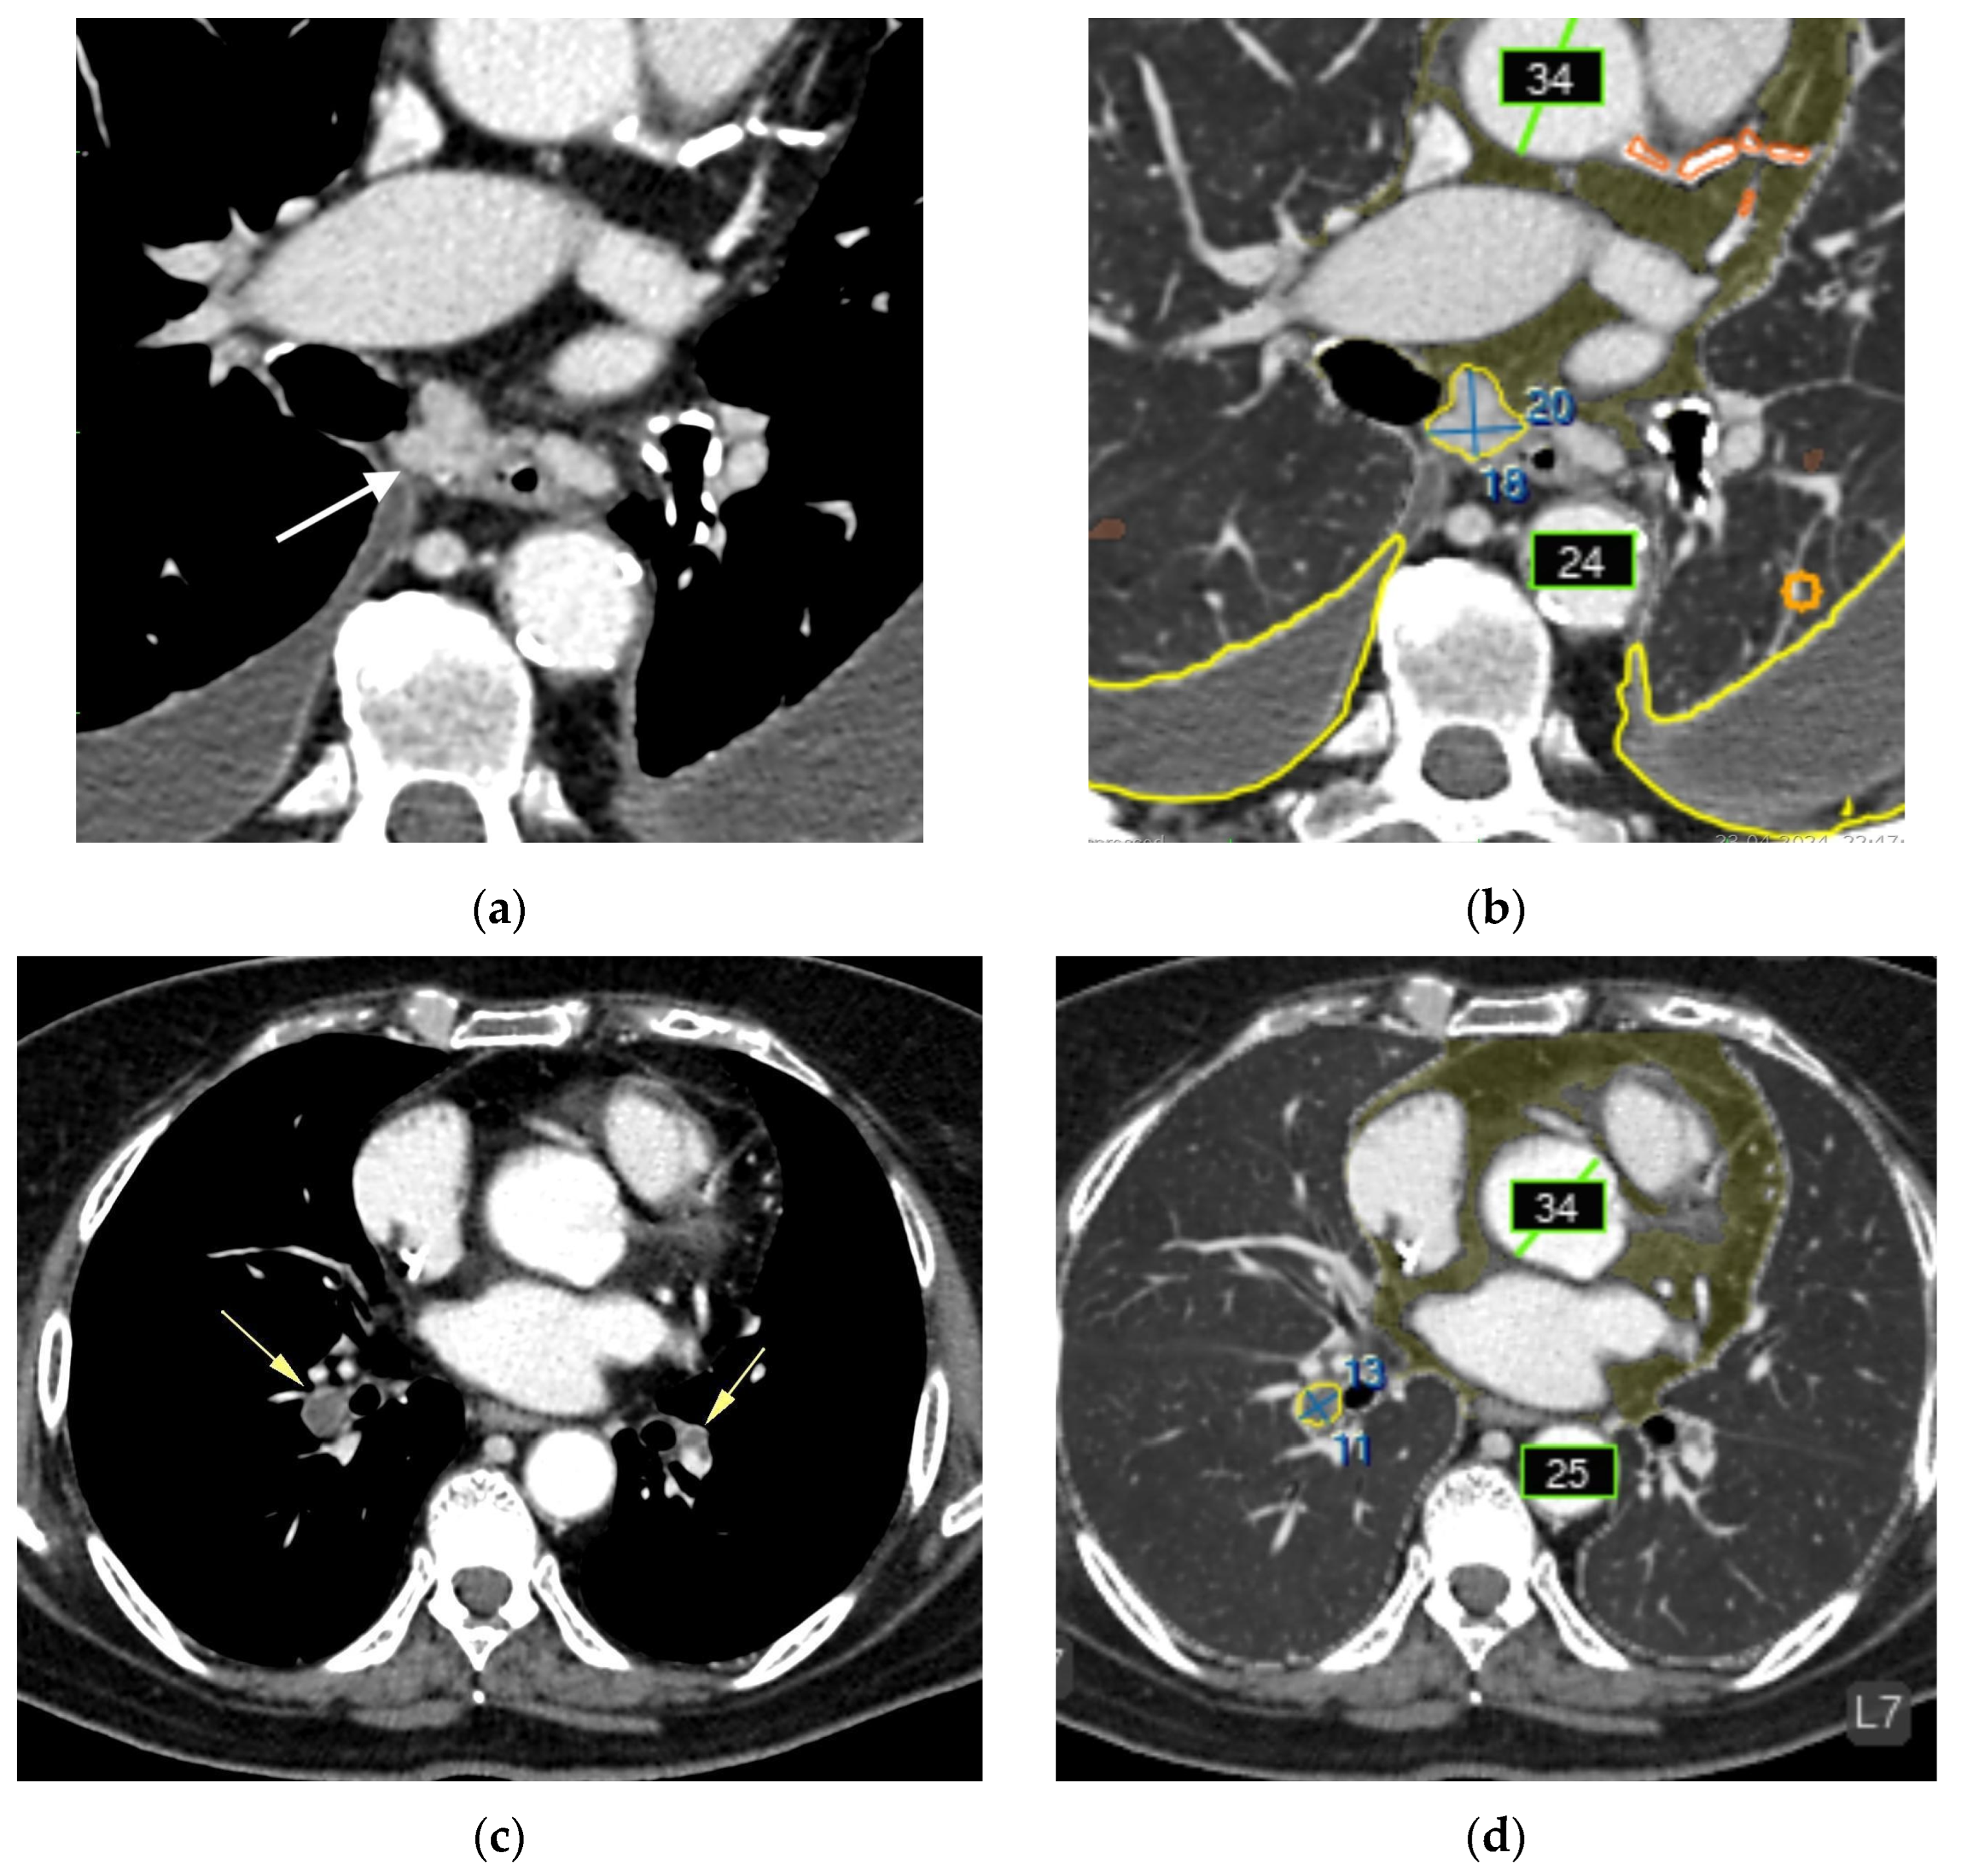

- Intrathoracic lymph nodes (16);

- Pulmonary nodules (15);

- Impaired aeration (15);

- Aortic dilatation/aneurysm (10);

- Adrenal thickening (10) (Figure 5).